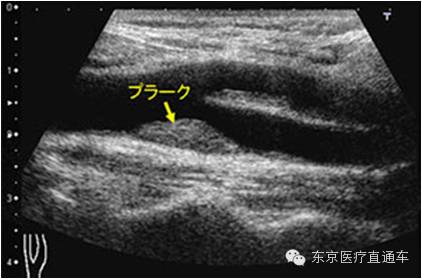

4:颈动脉超声波检查

颈动脉超声波是一种利用超声波来检查颈动脉有无狭窄、硬化的检查项目。由于颈动脉是心脏往胸部输送血液的重要血管通道,因此可以通过该项检查来推断心脏乃至全身的动脉硬化程度。